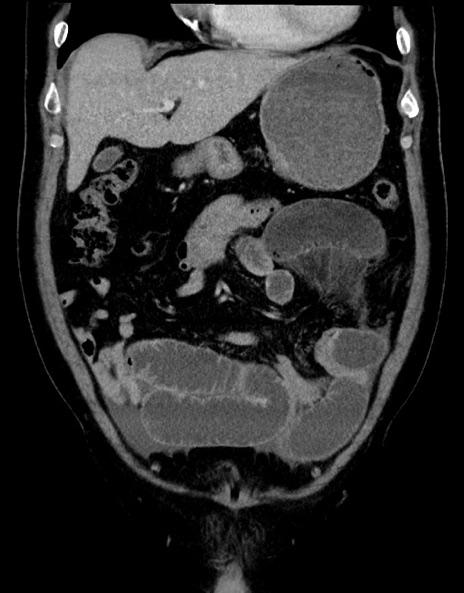

症例15(冠状断像)

【症例】70歳代男性

【主訴】腹痛

【現病歴】今朝から腹痛あり。全体的に痛い。特に左上の方。排ガスが今日はない。冷や汗が出る。

【既往歴】直腸癌術後

【身体所見】左側腹部〜上腹部に圧痛あり。腹膜刺激症状明らかなではない。軽度反跳痛。左下腹部に術後瘢痕あり。

【データ】WBC 7700、CRP 0.02